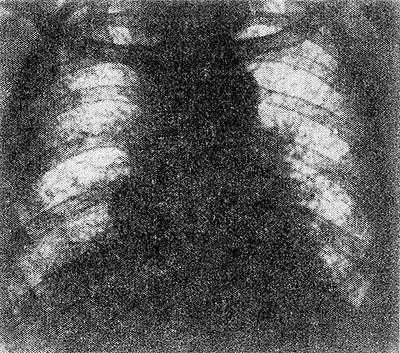

Рис. Рентгенограмма грудной клетки больного с синдромом Хаммена — Рича (прямая проекция): резкое усиление и тяжисто-ячеистая деформация легочного рисунка.

Диагноз устанавливают на основании характерных клин, признаков. Среди дополнительных методов исследования важным является рентгенологический. Ранними рентгенологическими признаками Хаммена-Рича синдрома являются усиление и деформация легочного рисунка, обычно выявляемые в нижних и средних отделах легочных полей. Прозрачность этих участков понижается за счет появления множества тяжистых теней, идущих радиально от корней к периферии по ходу бронхов и сосудов. Характерен сетчатый, ячеистый рисунок, обусловленный разрастанием соединительной ткани вокруг долек и ацинусов (рис.).

По мере прогрессирования процесса отмечается уплотнение теней корней и утолщение пристеночной, междолевой и диафрагмальной плевры; верхние отделы легких также постепенно вовлекаются в патологический процесс. На фоне усиленного и деформированного легочного рисунка появляются нечетко очерченные очаговые тени небольших и средних размеров, частично сливающиеся между собой. Подвижность диафрагмы уменьшается, реберно-диафрагмальные синусы частично, а затем полностью облитерируются.

При далеко зашедшем процессе в кортикальном слое легких по периферии легочных нолей появляются кистовидные полости, диаметром до 2—3 см, некоторые с уровнем жидкости. Томография (см.) и бронхография (ем.) позволяют иногда обнаружить цилиндрические, мешотчатые и смешанные бронхоэктазы, обычно в нижнемедиальных отделах легких. Характерным для течения. является неуклонное нарастание отмеченных рентгенологических изменений . является неуклонное нарастание отмеченных рентгенологических изменений .